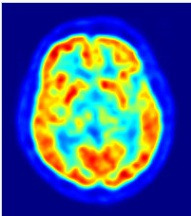

두뇌에서 방출한 양전자의 분포 패턴을 분석해 데이터를 구축하는 것으로 사고의 패턴을 추적하고

특정 사고에 두뇌가 어떤 부분이 관여하는도 알아낼 수 있다.

wikipedia_org_20170305_005409.jpg 양전자방사 단층촬영(PET)로 촬영한 뇌

MRI는 PET(양전자 방사 단층촬영)과 유사한 원리로 작동하는데, 더 정밀한 데이터를 얻을 수 있다.

환자의 머리를 자기장 속에 노출시키면 두뇌를 구성하고 있는 원자핵들이 자기장과 나란한 방향으로 정렬되고,

이때 라디오파 펄스를 환자 머리에 쏘이면 원자핵의 정렬 방향이 바뀌면서 라디오파의 에코(메아리)가 생기면서 이 신호를 감지하면 두뇌에 어떤 물질이 있는지 알 수 있다.

두뇌의 활동은 산소의 소비와 관련이 높으므로 , MRI 의 기능을 산소를 지닌 혈액에 집중시키면

혈액이 밀집한 부위를 추적함으로써 두뇌의 사고 과정을 알아낼 수 있다.